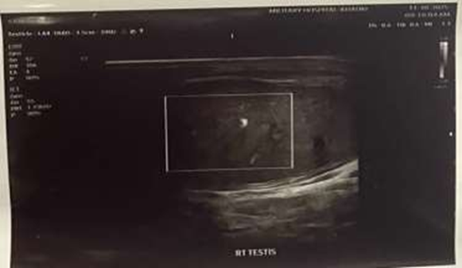

Scrotal Doppler ultrasound

The left testis was normal in size and shape but showed a heterogeneous echotexture with absent vascularity on color Doppler. A minimal hydrocele was noted in the left hemiscrotum. Twisting of the cord structures was also observed at the superior aspect of the left testis, displaying a characteristic “whirlpool” appearance.

Figure 1: USG Scrotum showing absent testicular vascularity Secondary Hydrocele.